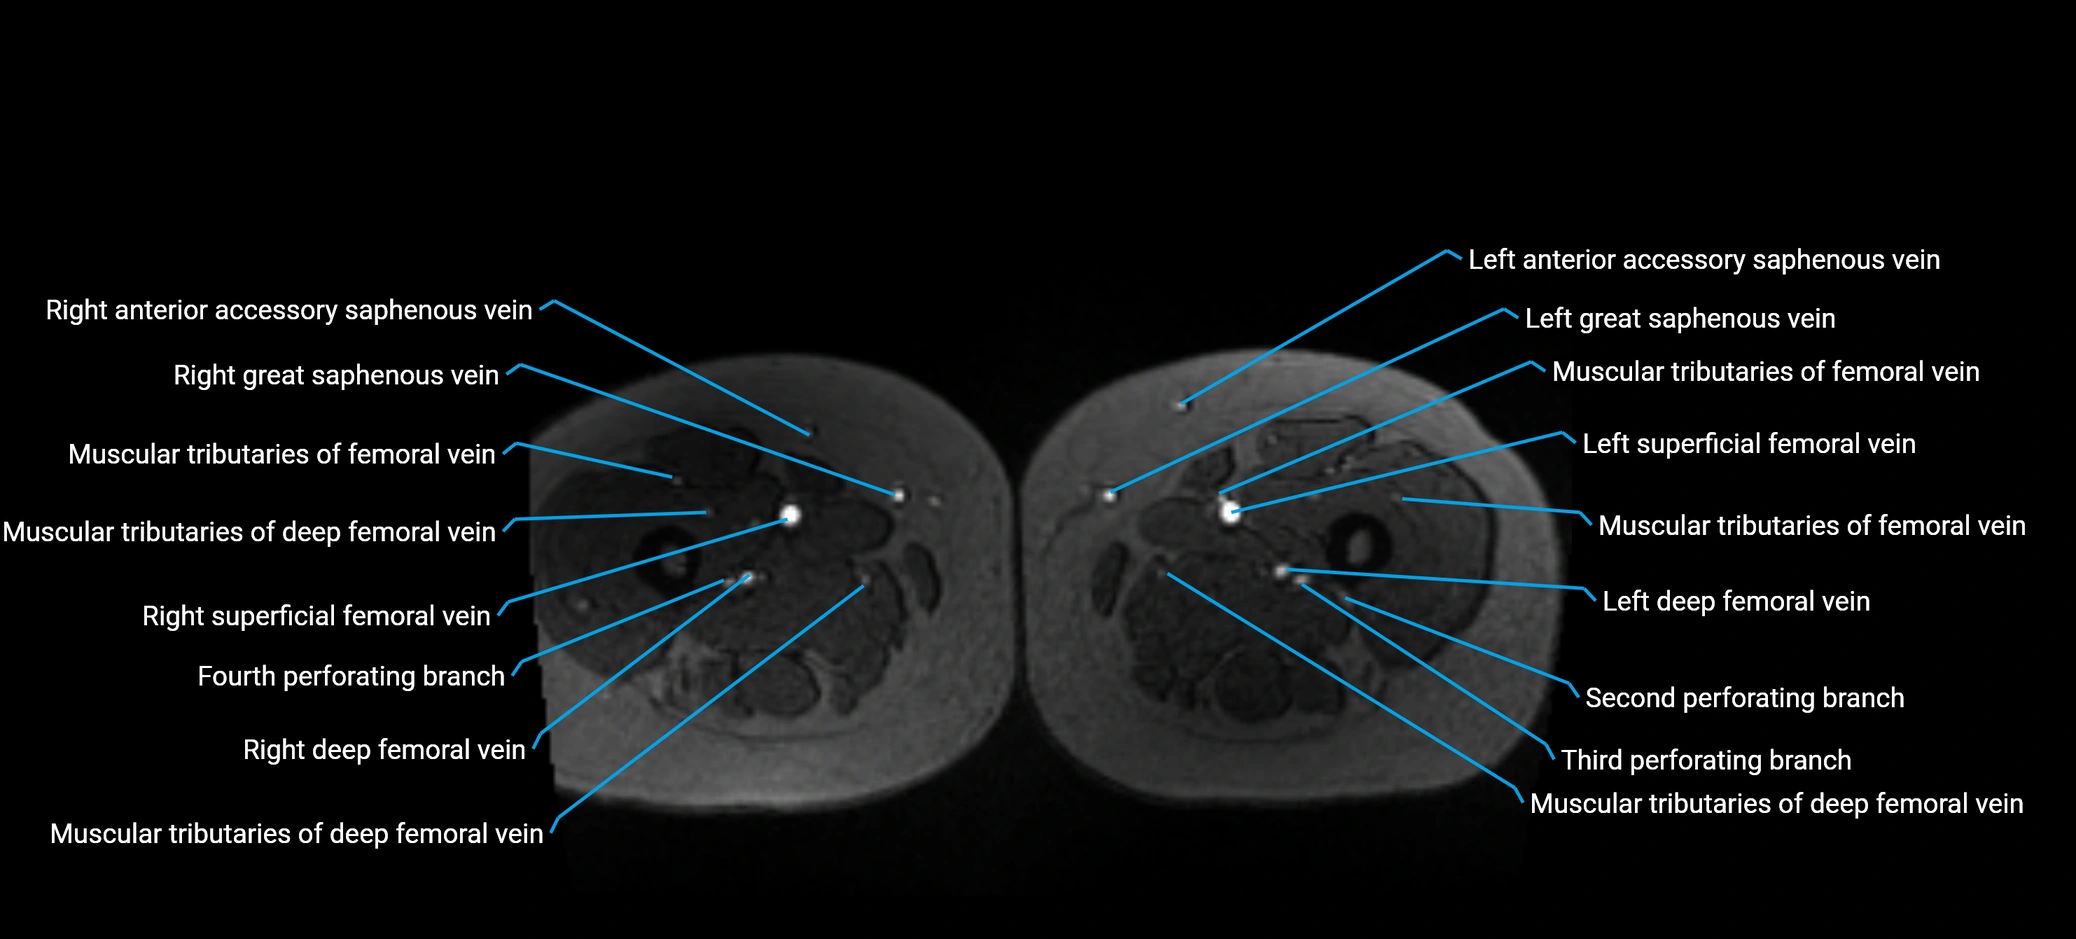

MRI image

image